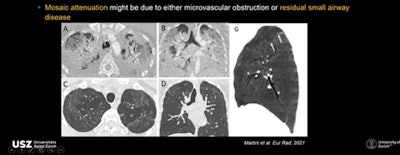

(A) CT shows a 65-year-old patient in subacute stage with bilateral ground-glass opacities and consolidation and in posterior lung area, signs resembling COP. (B) After six months, consolidation has mainly resolved but some ground-glass opacities remain in posterior right zone of lung and within this, an area of bronchial distortion.Another interesting three-month finding on CT is mosaic attenuation pattern with areas of hypoattenuation in patients who had severe or critical disease, noted Martini. This mosaic attenuation can be best visualized in minimum intensity projection (MIP) and might be due to either microvascular obstruction or residual small airway disease.

CTs show mosaic attenuation pattern due to microvascular obstruction or residual small airway disease.

CTs show mosaic attenuation pattern due to microvascular obstruction or residual small airway disease.At 12-month follow-up, most changes have resolved with only 24% of patients showing abnormal CT findings, and the spectrum of these findings also changing, noted Martini. Typical fibrotic-like features such as interlobular septal thickening and reticular opacity almost disappear by month nine to leave only GGO as the predominant residual finding. Established fibrosis or interstitial thickening is not observed.